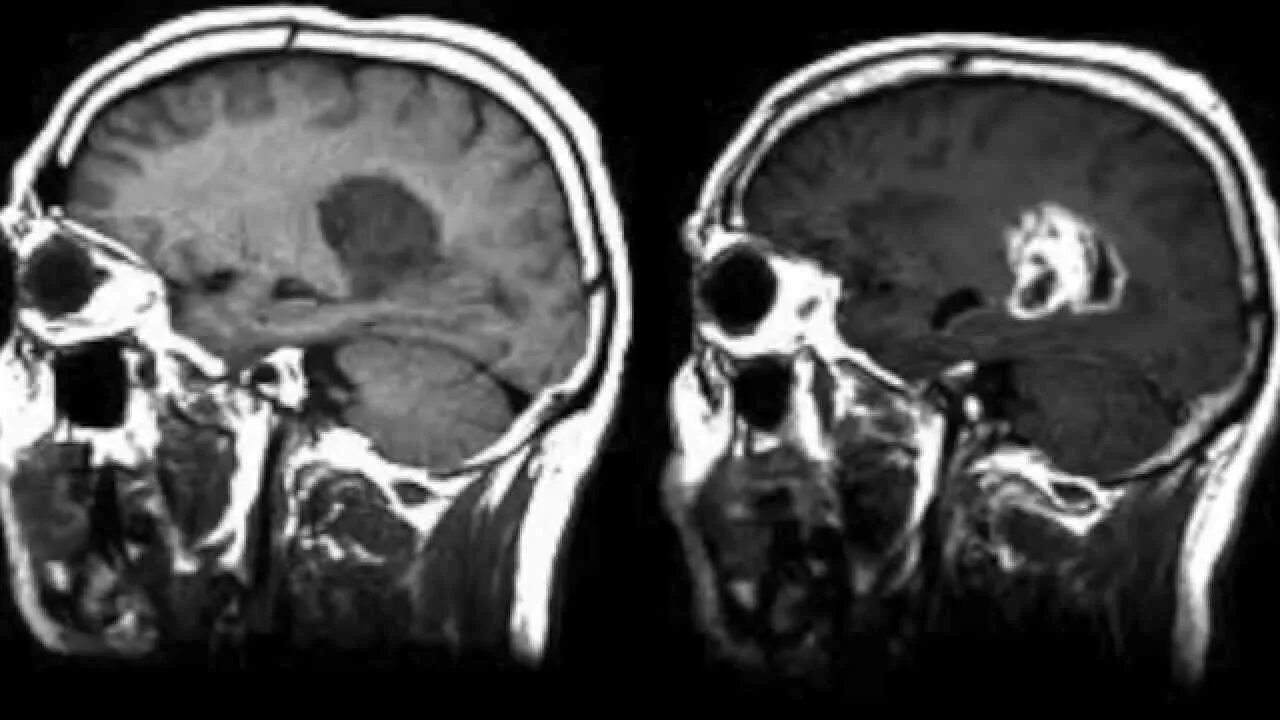

Мрт с контрастом в каких случаях